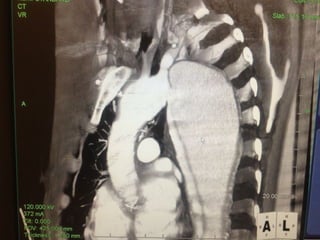

• Preoperative CT 1mm imaging to include pelvisPreoperative CT 1mm imaging to include pelvis